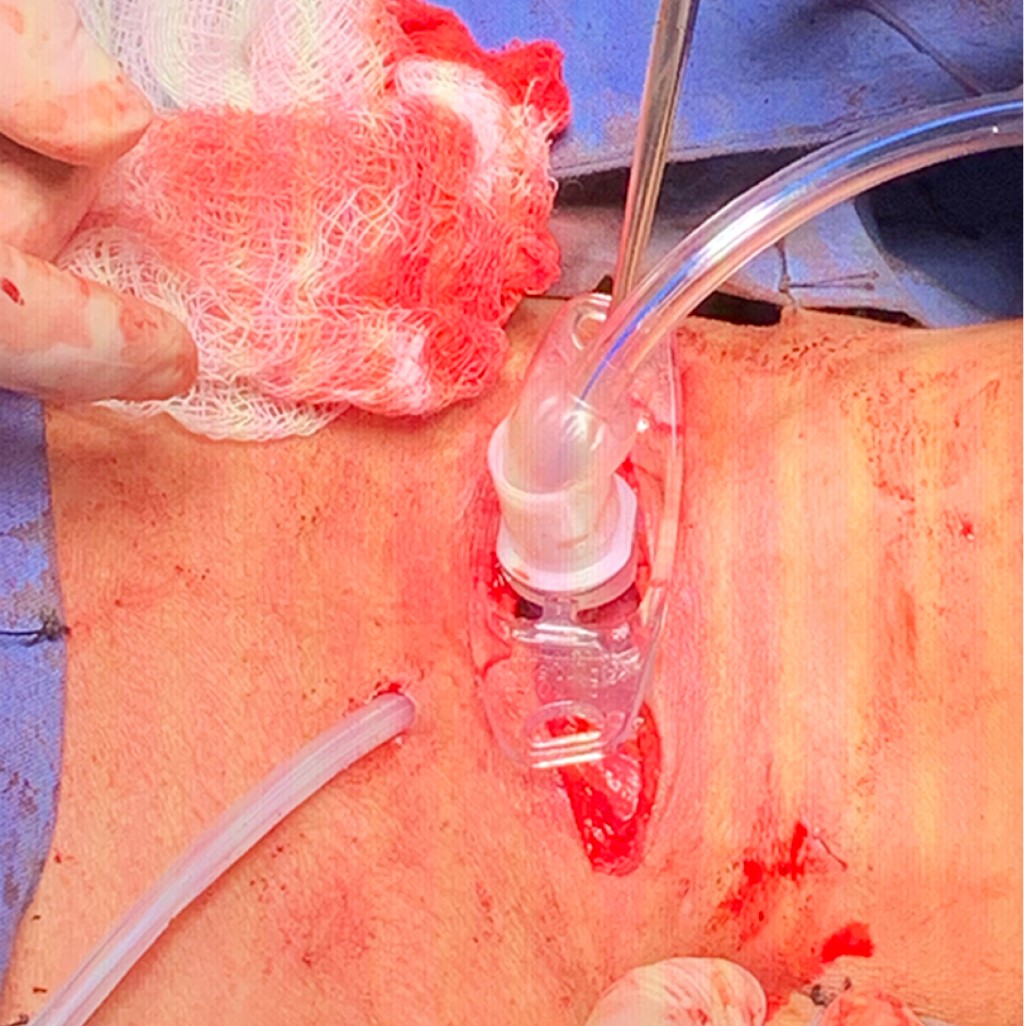

Se realizó nueva fibrobroncoscopia el 26 de abril de 2021 con hallazgo de fístula traqueoesofágica a 4 cm de cuerdas vocales de 4 cm de longitud, tráquea con 10 anillos traqueales libres a carina principal, por lo que se decidió ingresar a la paciente a nuestro instituto para manejo quirúrgico realizando cierre de fístula traqueoesofágica más cierre de estoma traqueal y colocación de traqueostomía en segundo anillo traqueal; se dejó cánula Portex 7 fenestrada sin globo. Se realizó un abordaje por cervicotomía transversal con hallazgos transoperatorios de abundantes adherencias paratraqueales y paraesofágicas, fístula traqueoesofágica de 3 cm de longitud (Figura 3). Cierre de esófago con sutura PDS 3-0 y cierre de pared posterior de tráquea con misma sutura con interposición de colgajo de músculo esternotiroideo entre ambos (Figura 4), estoma traqueal previo a nivel del cuarto anillo traqueal, el cual se recolocó a nivel de segundo anillo traqueal (Figura 5) y sangrado transoperatorio mínimo. Evolución posquirúrgica adecuada. Se realizó esofagograma de control a los siete días sin evidencia de fuga y con adecuado pase del medio de contraste (Figura 6). Se inició dieta con adecuada tolerancia y se egresó al día ocho posoperatorio sin complicaciones.